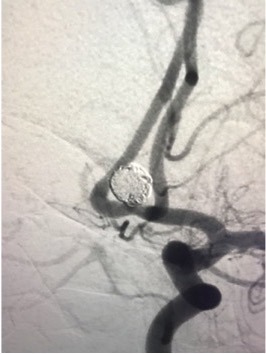

Gehirnaneurysma (Clip, Coil, Flow Diverter)

Als klinisch-wissenschaftlicher Neurochirurg habe ich großes Interesse daran, meine klinischen Aufgaben durch Wissenschaft und Forschung in den von uns behandelten neurochirurgischen Erkrankungen zu ergänzen. Seit meinem Studium und postgraduellen Ausbildung war ich an Grundlagenforschung, klinischer und translationaler Forschung beteiligt und habe bisher mehr als 450 wissenschaftliche Veröffentlichungen zur medizinischen Fachliteratur beigetragen sowie erfolgreich kompetitive Drittmittel eingeworben. Wir haben die Behandlung traumatischer zerebrovaskulärer Erkrankungen, genetische Polymorphismen im Zusammenhang mit zerebralen Aneurysmen und aneurysmatischen Subarachnoidalblutungen sowie die Behandlung von Thrombozytenaggregationshemmern im Zusammenhang mit der Flow-Diverter-Behandlung von zerebralen Aneurysmen untersucht, um nur einige Projekte zu nennen.